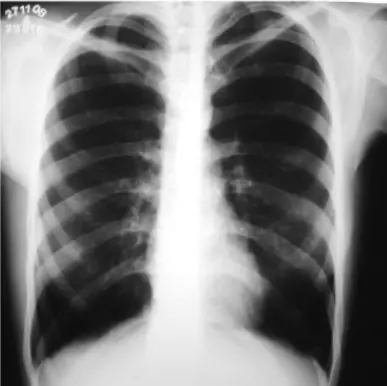

Principal alteração na radiografia de tórax do paciente com DPOC

Hiperinsuflação pulmonar